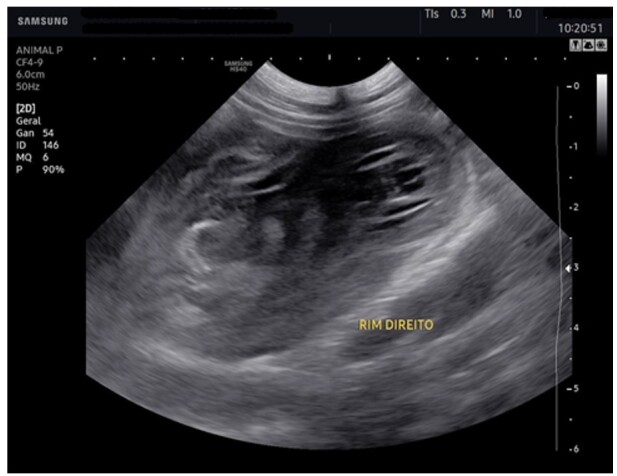

Abstract Image